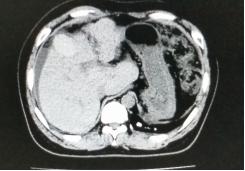

我们将这种方法应用到150 多例没有艾滋病病毒感染的一般肝硬化患者,结果收到更好疗效[19-20]。例如1例患者男,56 岁,失代偿肝硬化大量腹水合并脐疝(图1)。 CT检查提示肝脏明显萎缩,肝脏体积1302 ml,大量腹水, 脾脏肿大(图2)。我们对患者进行脾切除加脐疝修补,自体骨髓经门静脉输注治疗。手术后3 个月,肝功能Child-Pugh分级从C级转成*级A**,手术后1 年,肝功能正常,腹部伤口愈合良好(图3)。CT检查提示肝脏明显增大,体积1796 ml,腹水基本消失(图4)。对于肝功能C级的患者手术风险比较高,围手术期输注白蛋白,凝血酶原复合物,纤维蛋白原,改善肝脏功能,手术中经胃网膜右静脉插管埋置骨髓输注装置,输注自体骨髓。随着自体骨髓干细胞在肝内发生复杂的变化,肝硬化组织中的胶原纤维被降解和吸收,肝脏组织的增生和体积增大,肝功能好转,门静脉压力会逐渐降低。但是在手术和自体骨髓经门静脉输注后1到2 年内,仍然有可能随时发生上消化道出血,需要经胃镜检查,套扎食管黏膜下明显曲张的静脉血管。这样脾脏切除解除脾功能亢进,不做贲门周围血管离断,减少了手术损伤。食管黏膜下静脉曲张用胃镜下套扎治疗。待肝硬化的逐渐逆转,食管黏膜下静脉曲张程度将会逐渐减轻。

图2.术前腹部CT断层照片

图4.1年后对比手术前同一部位CT断层照片